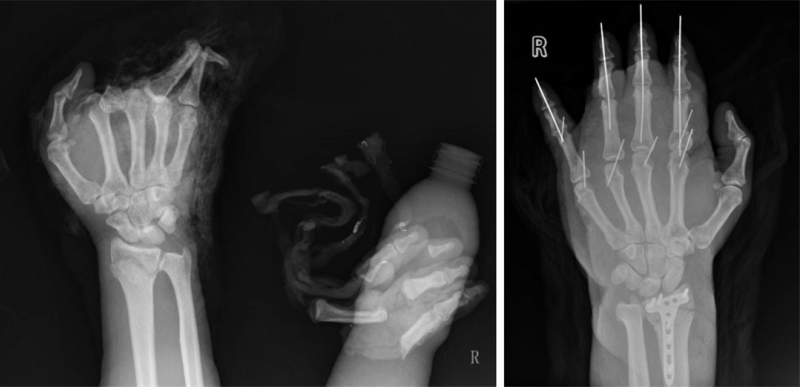

术前及术后X线片对比。

当天下午4点,手术开始,三组医师同时上台。徐俊涛、李英负责创面清创;于胜军、马振杰负责切取双足背静脉网,分离双侧股前外皮瓣;付胜强、李晓负责血管及皮瓣的吻合,显微镜下吻合断裂及移植的血管多达28条。为了减轻离断指体缺血损伤,术中一直使用无菌冰袋进行冷敷。经过彻夜鏖战,手术结束时已是第二天的早上9点,患者的四根手指被接了回去,离断的手指颜色由苍白转为红润,血运慢慢恢复了正常,所有人都松了一口气,手术初战告捷。